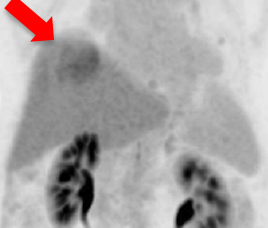

Improvement is seen in most of the lesions on F-18-PSMA PET/CT (indicated by red arrows) after Lu-177 PSMA radionuclide therapy. Lesions become metabolically inactive and less active on post-treatment scan.